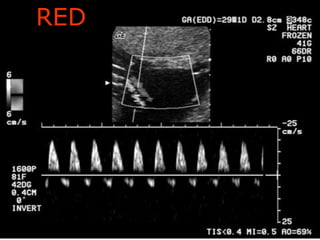

RED

Aboubakr Elnashar

End Diastolic flow

 In IUGR and/or PET:

reduced, then

absent (AED) or

reversed (RED) in severe cases

 Absent or reversed:

Fetal distress is almost certain:

Immediate BPP or NST or

Delivery may be indicated.

End Diastolic flow In IUGR and/or PET: reduced, then absent (AED) or reversed (RED) in severe cases  Absent or reversed: Fetal distress is almost certain: Immediate BPP or NST or Delivery may be indicated. Aboubakr Elnashar